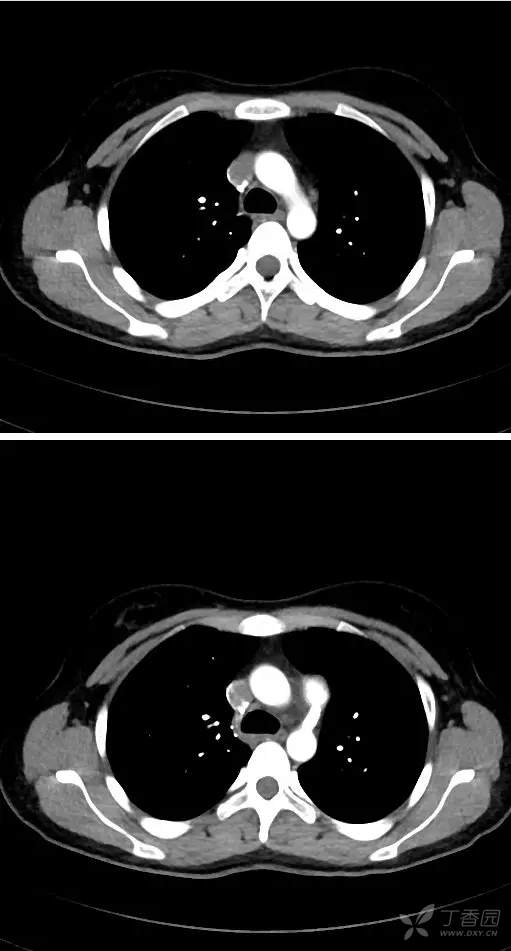

ct看少见病:5分钟学会ct看先心病--动脉导管未闭.

图片尺寸511x951![【读片】心脏ct [病例帖]](https://imgs.wantubizhi.com/img/ADDA3C5D760C6828B77B505A29D43E834B5BE20D216BE695F6046D8688E31ADE9836F0012187392BC89864F34AEC8DF7C8D25B97D3F6EF38ADFC56078AF07FFD1DA7B2DF338D70FB9D85D7BE2B8E0B520212AC83678AE6AAAAAFE634A8188457)

【读片】心脏ct [病例帖]